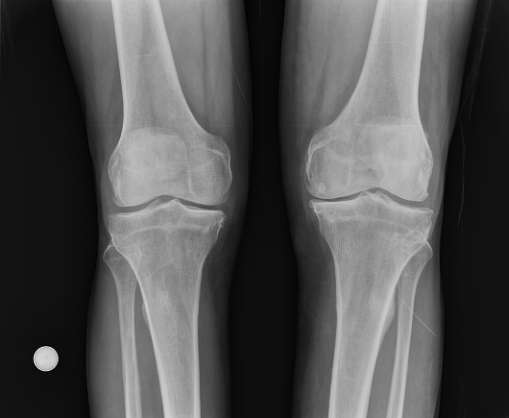

Describen polímero único y su rendimiento en Journal of the American Chemical Society. La forma más común de enfermedad común y la principal causa de discapacidad en los ancianos, la osteoartritis (OA) afecta a unos 27 millones de estadounidenses y 200 millones de personas en todo el mundo. Caracterizado por el dolor y la inflamación, la enfermedad surge en la mano, cadera, rodilla y otras articulaciones comúnmente utilizados donde la degradación del cartílago y los resultados de líquido sinovial en la abrasión de hueso con hueso. Los tratamientos van desde medicamentos anti-inflamatorios para el reemplazo total de la articulación.

aceite sinovial, aceite en las articulaciones, cualquier aceite q me unte en las coyonturas sirbe oara lubricar lis huesos, liquido sinovial en acipuntura, proyeccion AP bilateral rodillas en carga